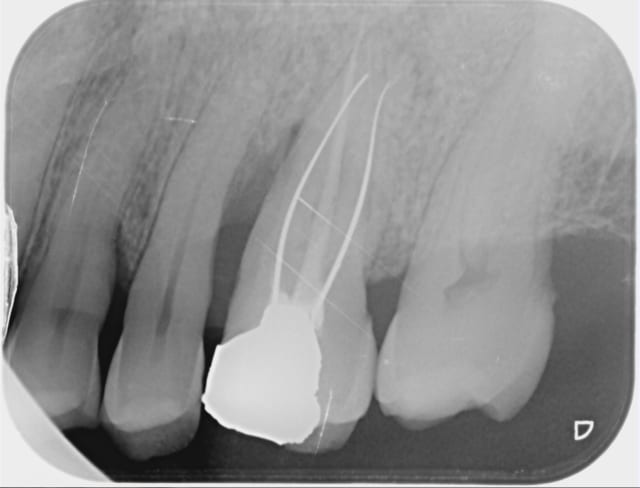

Voici le résultat d'une 3ème séance de recherche du MV 2 le vague à l'âme expliquant l'absence de digue , et mv 2 que j'aurai nommé le CCE pour casse couille endodontique mais n'étant pas endo exclusif je reste courtois avec cette désespérance souvent absente radiologiquement après obturation et dont le trajet incertain me laisse rêveur , quand à la guérison de l'image en mésial prions pour que Saint NaOCl et Saint EDTA veillent sur nous .

Bref cônes d'argent présents MV1 et DV , palatin ?!?!? : aucune image radio , à tout les coups mon MV 2 sera insuffisant et je serai le maillon faible ...)))

Tu remarqueras qu'il n'y a aucune image apicale face aux cônes d'Ag .

Egalement les rapports curieux entre mv1 et mv2 , je suis arrivé à virer le 1/3 milieu du cône qui se trouve dans mv1 et je suis au bout du mv2 que j'ai pénétré facilement après l'avoir cherché 3 séances...